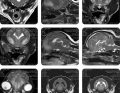

Niespodzianki radiologiczne – ataki duszności u psa z niestabilnością szczytowo-obrotnikową